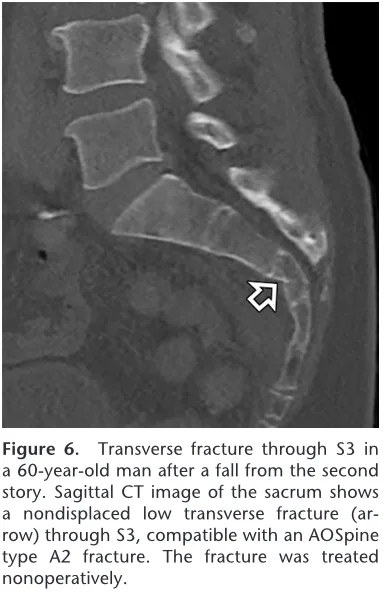

仙骨骨折の急患

引用元:Dreizin D. CT of sacral fractures: Classification systems and management. Radiographics. 2022. 42.

救急搬送された患者さんを診察すると, 仙骨部に明らかな圧痛.

骨折を疑いCTをオーダーすると, 予想通り仙骨(第3仙椎)骨折でした.

独居で, 疼痛が強く動けないため入院加療としました.